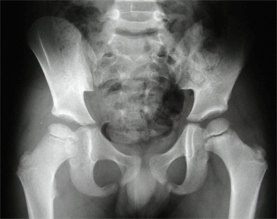

La radiographie standard : les signes de la maladie

Une radiographie du bassin de face en rotation neutre des hanches, et une radiographie du bassin de face, incidence « grenouille » (montrant les têtes fémorales de profil), représentent le bilan radiographique initial d’une OPH.

Aux premiers stades de la maladie, la radiographie est normale.

Qu'est-ce qu'une radiographie normale de hanche : les repères essentiels sont les suivants :